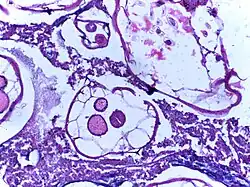

![]() |

Rhinosporidiosis | Section of a polyp containing Rhinosporidium seeberi | Category: Histopathology of rhinosporidiosis | Rhinosporidiosis |